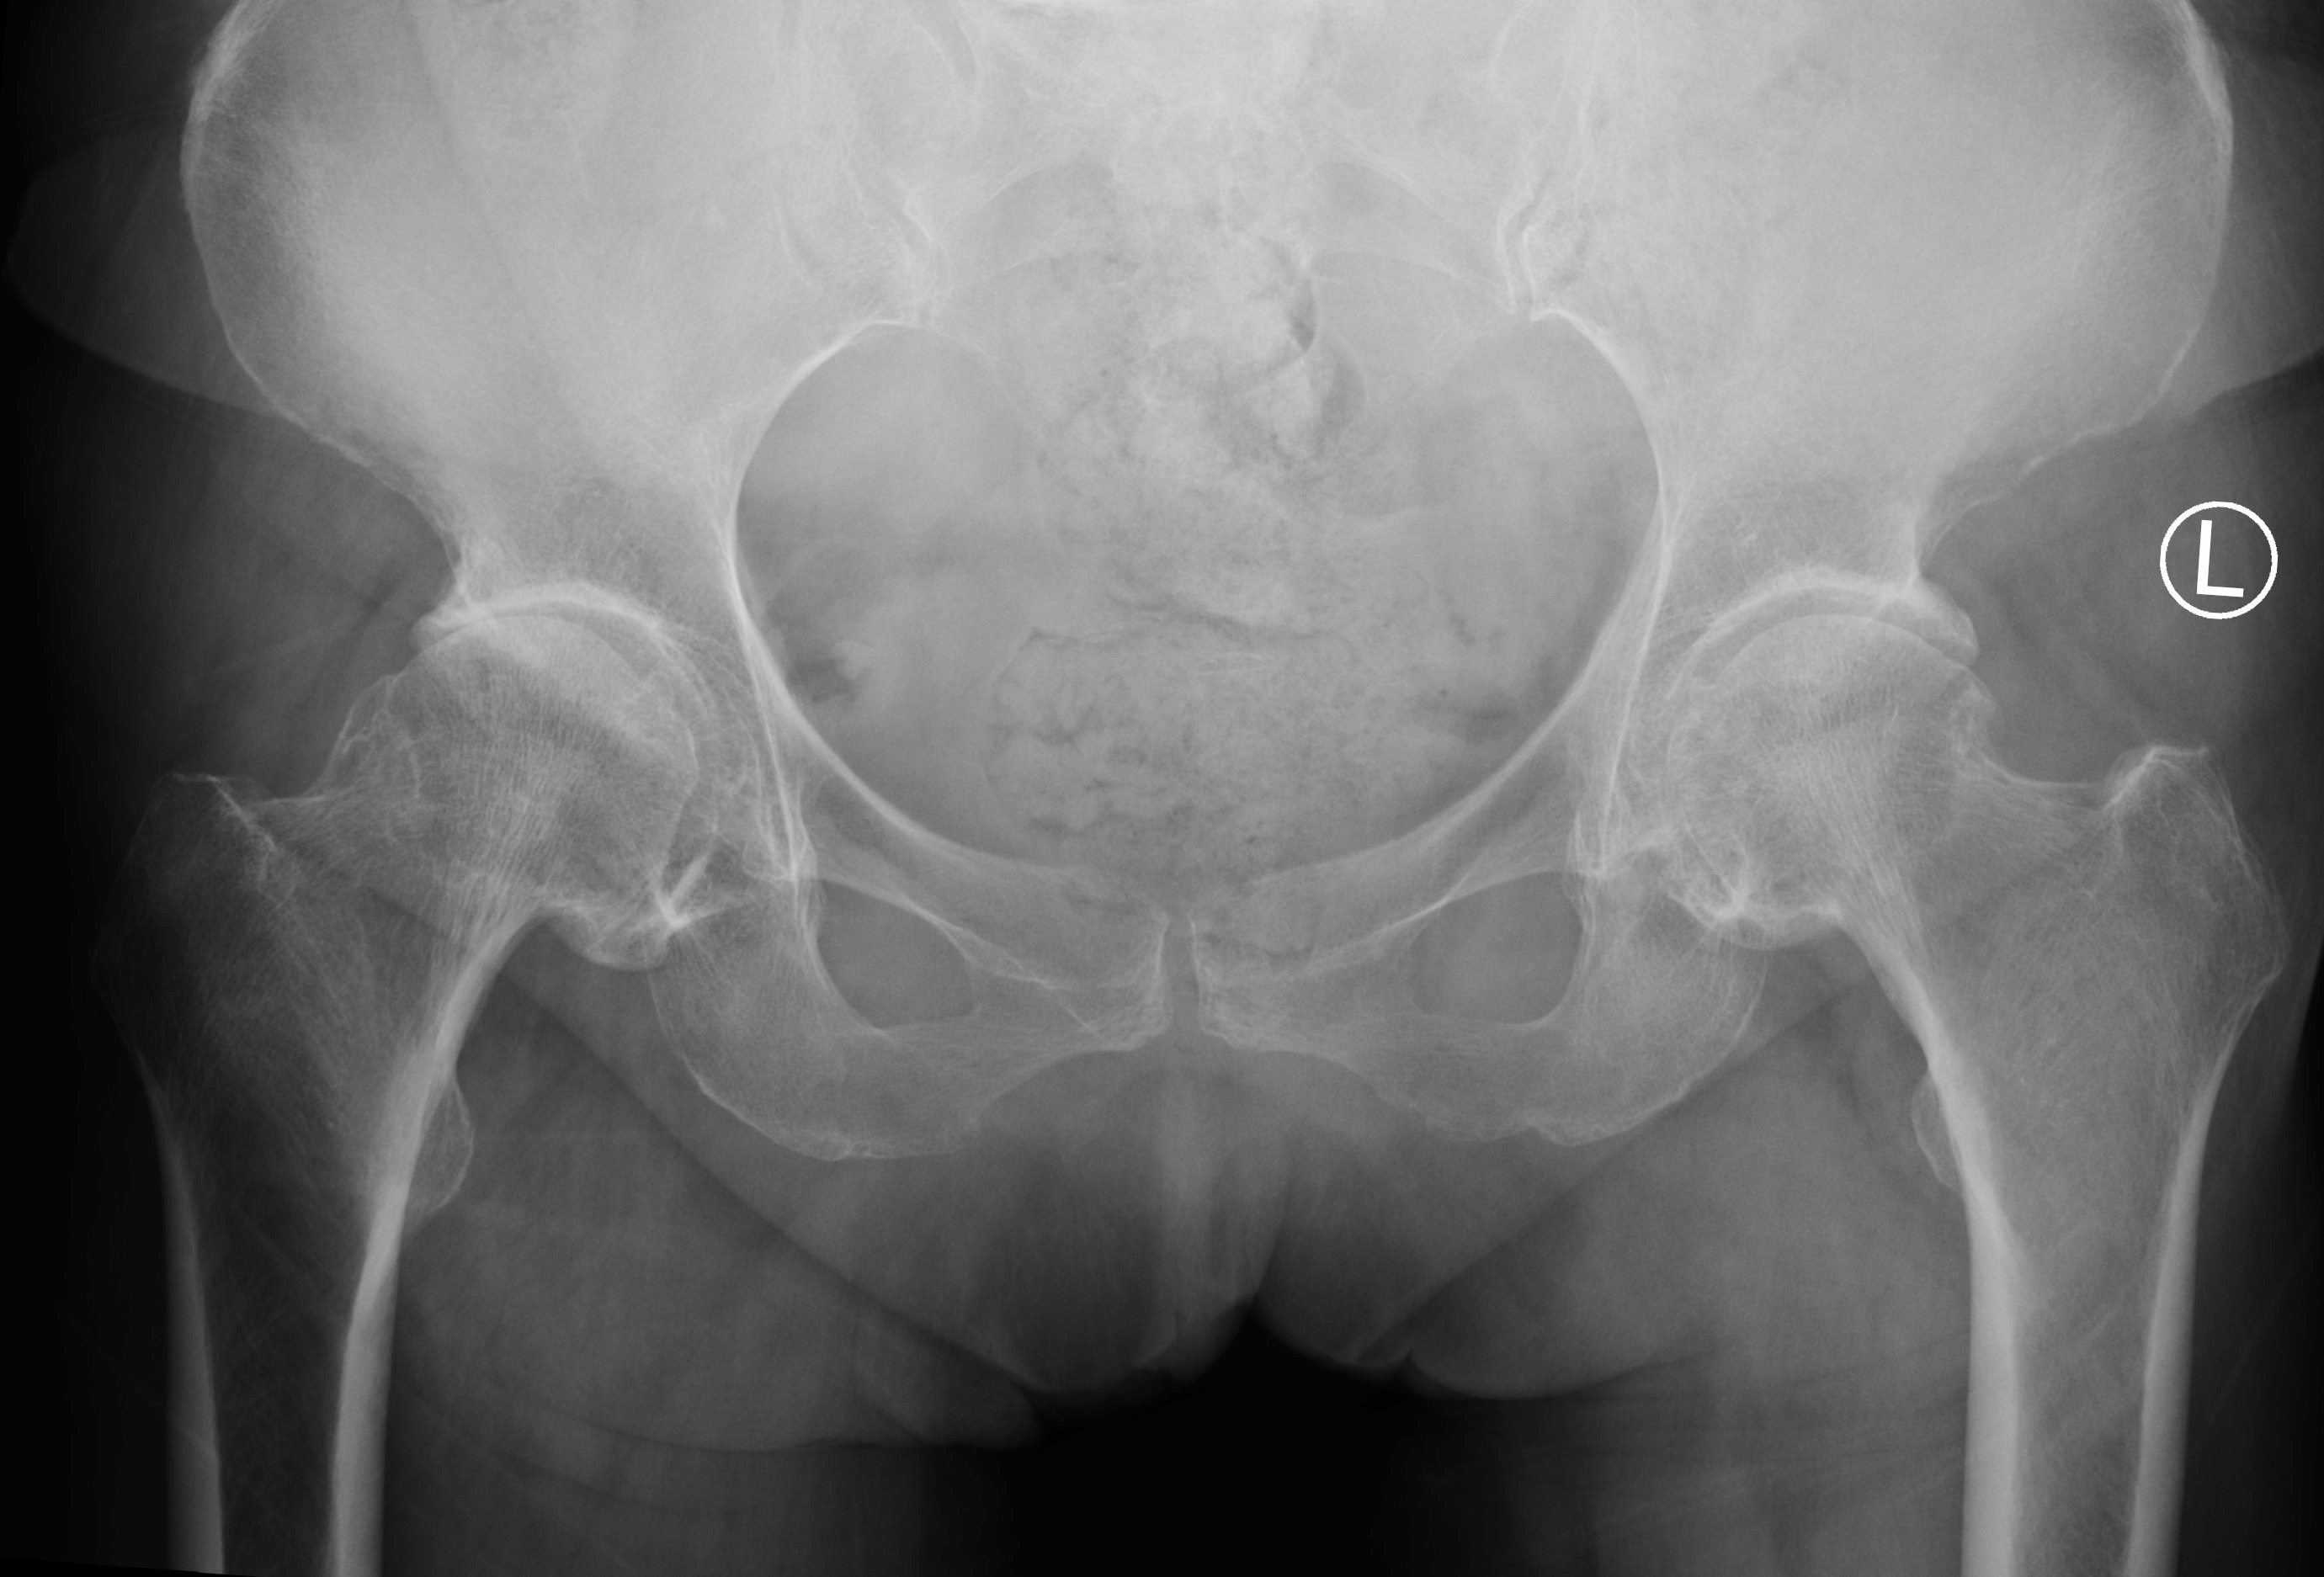

该患者为一名68岁女性,患髋关节骨性关节炎多年(图1),常年的疼痛和活动受限严重影响了患者的生活质量。在术中,手持导航系统可以显示髋臼磨挫和髋臼杯假体的安放角度,并显示髋关节的偏心距以及下肢长度的重建情况。手持导航仪上的实时反馈数据,可以将假体安放的位置和角度精确到1毫米和1度,从而最大程度地避免了人工操作的误差。在此导航系统的辅助下,患者的假体被安放到了准确的位置,下肢长度和偏心距得到了重建,并获得了非常满意的髋关节活动度和稳定性。手术仅用时60余分钟,与传统导航相比缩短了手术时间。患者术后的影像学结果显示,假体的位置、角度和肢体长度都非常理想(图2)。手术当天晚上患者即可下地活动,住院仅2天后,患者即平稳出院回家。

图1. 患者术前X光片。女性,68岁,双侧髋关节骨性关节炎。